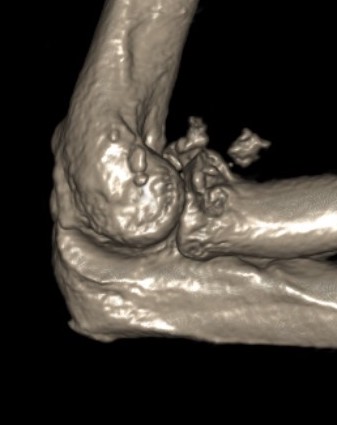

Complex Elbow Dislocation APComplex Elbow Dislocation Lateralelbo dis

Elbow dislocation with radial head fracture + coronoid fracture + MCL tear